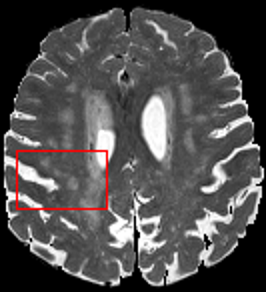

To test the impact of the iterative refinement on YODA’s translation quality, we compared regression and diffusion sampling on the RS data and present additional generation examples in Fig. 6. We observe that diffusion sampling visually resembles the appearance of the acquired images. Regression sampling preserves key anatomical features – the GM/WM boundary, WMHs (Fig. 4), the outline of the pallidum (Fig. 6) – but omits many high-frequency features. To investigate whether iterative refinement during diffusion sampling adds relevant and systematic medical information or only imitates acquisition noise, we performed ExpA sampling, i.e. averaging the output of several ( or ) diffusion trajectories. We observed a gradual loss of high-frequency details when increasing the (see also the supplementary video), indicating that the effect of the iterative refinement is non-systematic. For , the images are visually almost indistinguishable from the initial regression solution (see the supplementary video, and Fig.4 and 6). We directly compared the synthesis results of ExpA () and regression sampling quantitatively and found the differences to be minimal (SSIM: 99.73%, PSNR: 45.30 dB), i.e. diffusion sampling approaches the initial regression solution for a high . The quantitative analysis of the image quality (Tab. 1) showed that diffusion sampling impairs the assessed SSIM and PSNR in comparison to regression sampling for both the in- and external test sets, which we attribute to noise generation (Sec. 3.1). In turn, ExpA averages improved both metrics and, for , performed mostly on par with the regression solution in both test sets in terms of SSIM, while the PSNR in the RS was slightly increased (Tab. 1). However, we observed that ExpA sampling YODA improves the replication of systematic 3D low-frequency image intensity drifts (bias fields) due to the 3D synchronization in 2.5D diffusion sampling. Yet, this apparent advantage did not generalize to the external MBB dataset, as bias fields are MR protocol-specific.

We evaluated the impact of the proposed sampling methods on the performance of the independent, externally trained SHIVA-WMH tool as compared to manual reference labels (Tab. 1). Smoother images (higher or from regression sampling) yielded improved performance over those from diffusion sampling.

To assess the suitability of YODA-generated images for WMH detection independent of segmentation tools, we also calculated the CNR (15) of WMHs. This confirmed that the contrast of WMHs is preserved in the regression images, whereas we noted slightly reduced WMH contrast for diffusion and ExpA-sampled images (Tab. 1).

On the RS data (Tab. 1), regression sampling of YODA significantly outperformed all competing methods both w.r.t. the image quality and – except the ALVR for MADM – downstream WMH segmentation, whereas the DB of Choo et al. [31] achieved an higher WMH CNR.

When analyzing the RS synthesis results (Fig. 4), we noted that most reference methods strive to imitate realistic images, but several artifacts can be observed such as hallucinated WMHs (SynDiff) and salt-and-pepper noise (SynDiff, I2I-Mamba, ResViT).